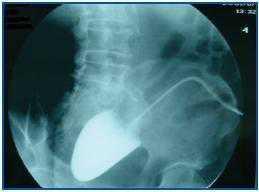

The patient decided to have the new peritoneal dialysis catheter implanted a month and a half after its removal (abdominal CAT showed no changes). The procedure was performed by general surgery, during which the lax adhesions that were observed were liberated. One month after implantation, we observed that draining was difficult. A peritoneography was taken (50ml iobitridol 300mg/l), revealing the presence of contrast limited to a small cavity (figure 1).

In light of these results, we decided to transfer the patient to HD and remove the peritoneal catheter, which was completely clogged by omental adhesions.

Figure 1.